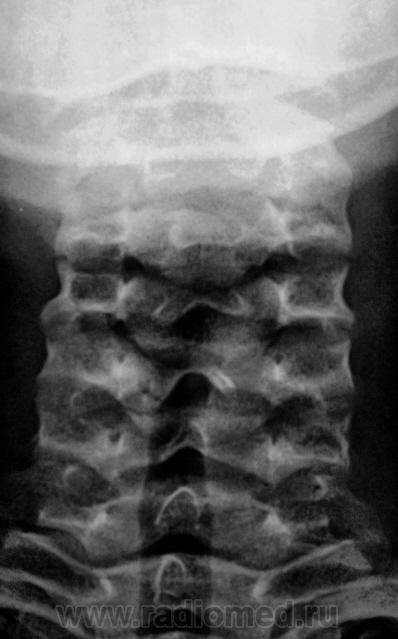

Спину бифида С2, по всей видимости можно считать возрастной нормой?

Покажите пожалуйста Спину бифида С2.

На мой взгляд, остистый отросток, как одно целое, не сформирован, по сравнению с другими остистыми отростками шейных позвонков.

Позволю не согласиться. У всех позвонков в сагитальной проекции в основании остистых отростков видим подчёркнутую линию "склероза", которая свидетельствует о слиянии "- двух сторон, и у С2 такая же картина.

На прямой слишком много всего наслаивается, достоверно выносить в заключение о незаращении по тому, что Вы отметили стрелочками невозможно. Из колег принявших участие в обсуждении тоже никто о spina bifida не высказался, скромно умолчали.

До 18 лет мы можем говорить только о незаращении (как временном факторе), ведь процесс развития костного аппарата еще продолжается. Вот стукнет 18, тогда и будем прподолжать разговор о spina bifida, так что Валентин Львоич прав по поводу именно возрастной особенности....

Остается не понятным, и это, изолированное увеличение расстояния между остистыми отростками (дугами) в сегменте С! - С2. Может быть "связочная несостоятельность" (нестабильность).

Я, прекрасно понимаю, что возраст - есть возраст, и возрастные особенности есть, но когда среди всего массива позвонков, в одном, замыкательная пластинка не дифференцируется, это как расценивать? Тем более, что "травматогенный" фактор, имел место быть.

- расхождение (в норме наслаиваются) верхних и нижних суставных фасеток атланта, относительная нечёткость замыкательной пластинки С3 (первая и третья группы стрелок).

Атланто-аксиальное (м/остистое) расстояние всегда больше, чем м/у остальными смежными позвонками (на то он и Крювелье! да и правило рычага - никто не отменял) (вторые стрелки)!